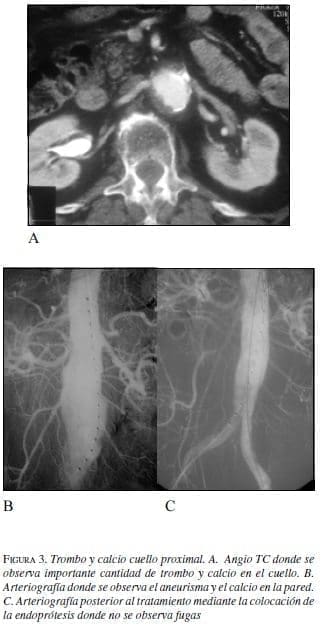

• Trombo mural:

la presencia de un trombo mural extenso puede no permitir un sellado seguro a largo plazo en el cuello proximal (12-14). Se debe ser cuidadoso en las maniobras de liberación y dilatación a fin de evitar embolias. De acuerdo con los estándares publicados. Se acepta como máximo la presencia de trombo cuyo espesor sea menor de 2 mm y que comprometa menos del 25% de la circunferencia aórtica.

• Calcificación:

La presencia de calcificación circunferencial en el cuello se reconoce como un factor pronóstico negativo de adecuado sellado, dejando fugas tipo 1. Se acepta como máximo tolerable sin riesgos la calcificación mural lineal menor del 25% de la circunferencia (figura 3).